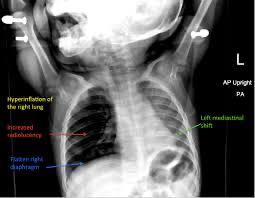

On-site hands on Bronchoscopy Training

Hands-on Training of Bronchoscopy/ Fellowship in Pediatric Pulmonology@Respiratory Foundation of India

After the completion of 12 weeks online classes,twice in a week, we provide Hand-on Training…